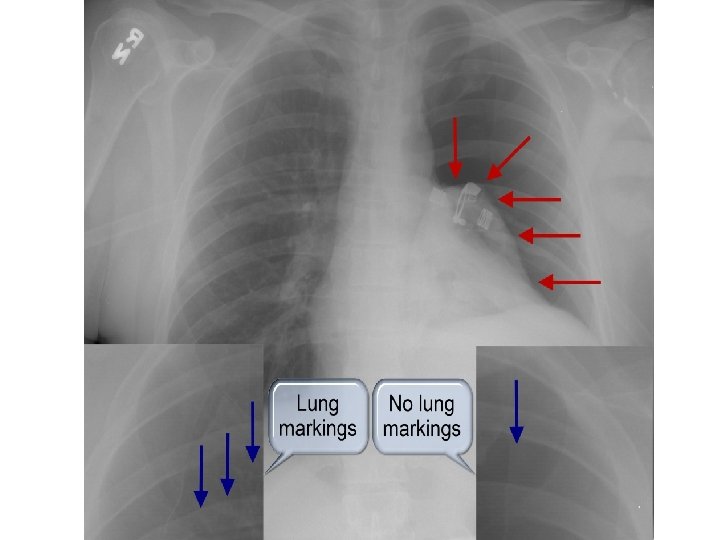

EKZAMINIMI RADIOLOGJIK

PNEUMOTORAKS I DYSHUAR Dispne e papritur/dhimbje kraherori Observim; Oksigjenim SHENJAT E PNEUMOTORAKSIT TE TENSIONIT? ? PO Dekompreso me shiringe me vrime te madhe, ne hapesiren 2/3 interkostale, ne linjen midklavikulare ne anen ku ka mungese ose reduktim te tingujve te frymemarrjes. JO Realizo nje X-ray. Bej drenazhin me tub! Realizo nje grafi kraherori (X-ray). Ka trashesi maksimale te pneumotoraksit (nga buza e mushkerise deri ne murin e kraherorit)?

< 2 cm (e vogel)? Pa simptoma Observim > 2 cm (e gjere)? Me simptoma Primare Aspirim me shiringe Rishikim klinik me perseritje te X-ray deri 7 -10 dite. Jo fluturime ajrore derisa X-ray te dale normal. Sekondare Drenazhim me tub